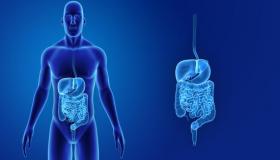

حسن صحة أمعائك .

الموجات فوق الصوتية في البطن